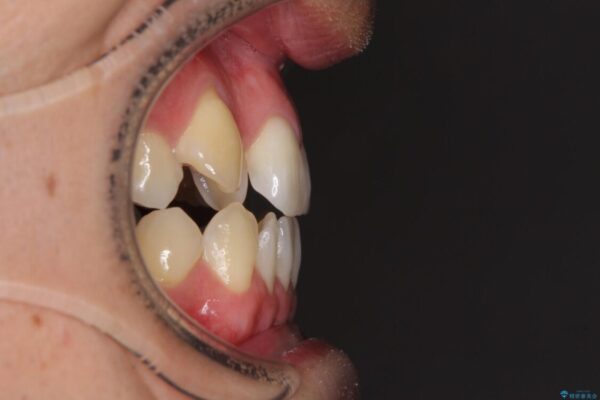

治療前

• 左右の八重歯が気になる ワイヤー装置での咬み合わせ改善 治療前画像